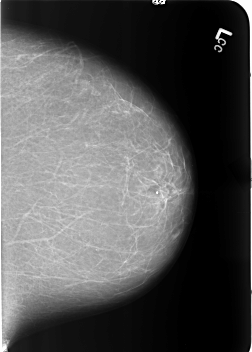

ics_version 1.0 filename B-3365-1 DATE_OF_STUDY 18 11 1997 PATIENT_AGE 41 FILM FILM_TYPE REGULAR DENSITY 1 DATE_DIGITIZED 13 7 1998 DIGITIZER LUMISYS LASER SEQUENCE LEFT_CC LINES 5632 PIXELS_PER_LINE 4032 BITS_PER_PIXEL 12 RESOLUTION 50 NON_OVERLAY LEFT_MLO LINES 5584 PIXELS_PER_LINE 4064 BITS_PER_PIXEL 12 RESOLUTION 50 NON_OVERLAY RIGHT_CC LINES 5744 PIXELS_PER_LINE 4008 BITS_PER_PIXEL 12 RESOLUTION 50 OVERLAY RIGHT_MLO LINES 5760 PIXELS_PER_LINE 4072 BITS_PER_PIXEL 12 RESOLUTION 50 OVERLAY |